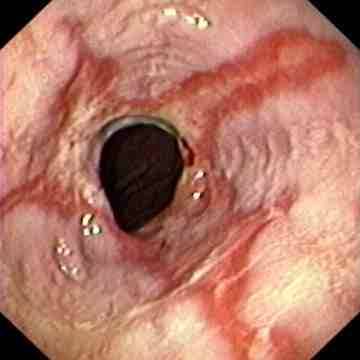

Reflux oesophagitis grade D according to the Los Angeles classification